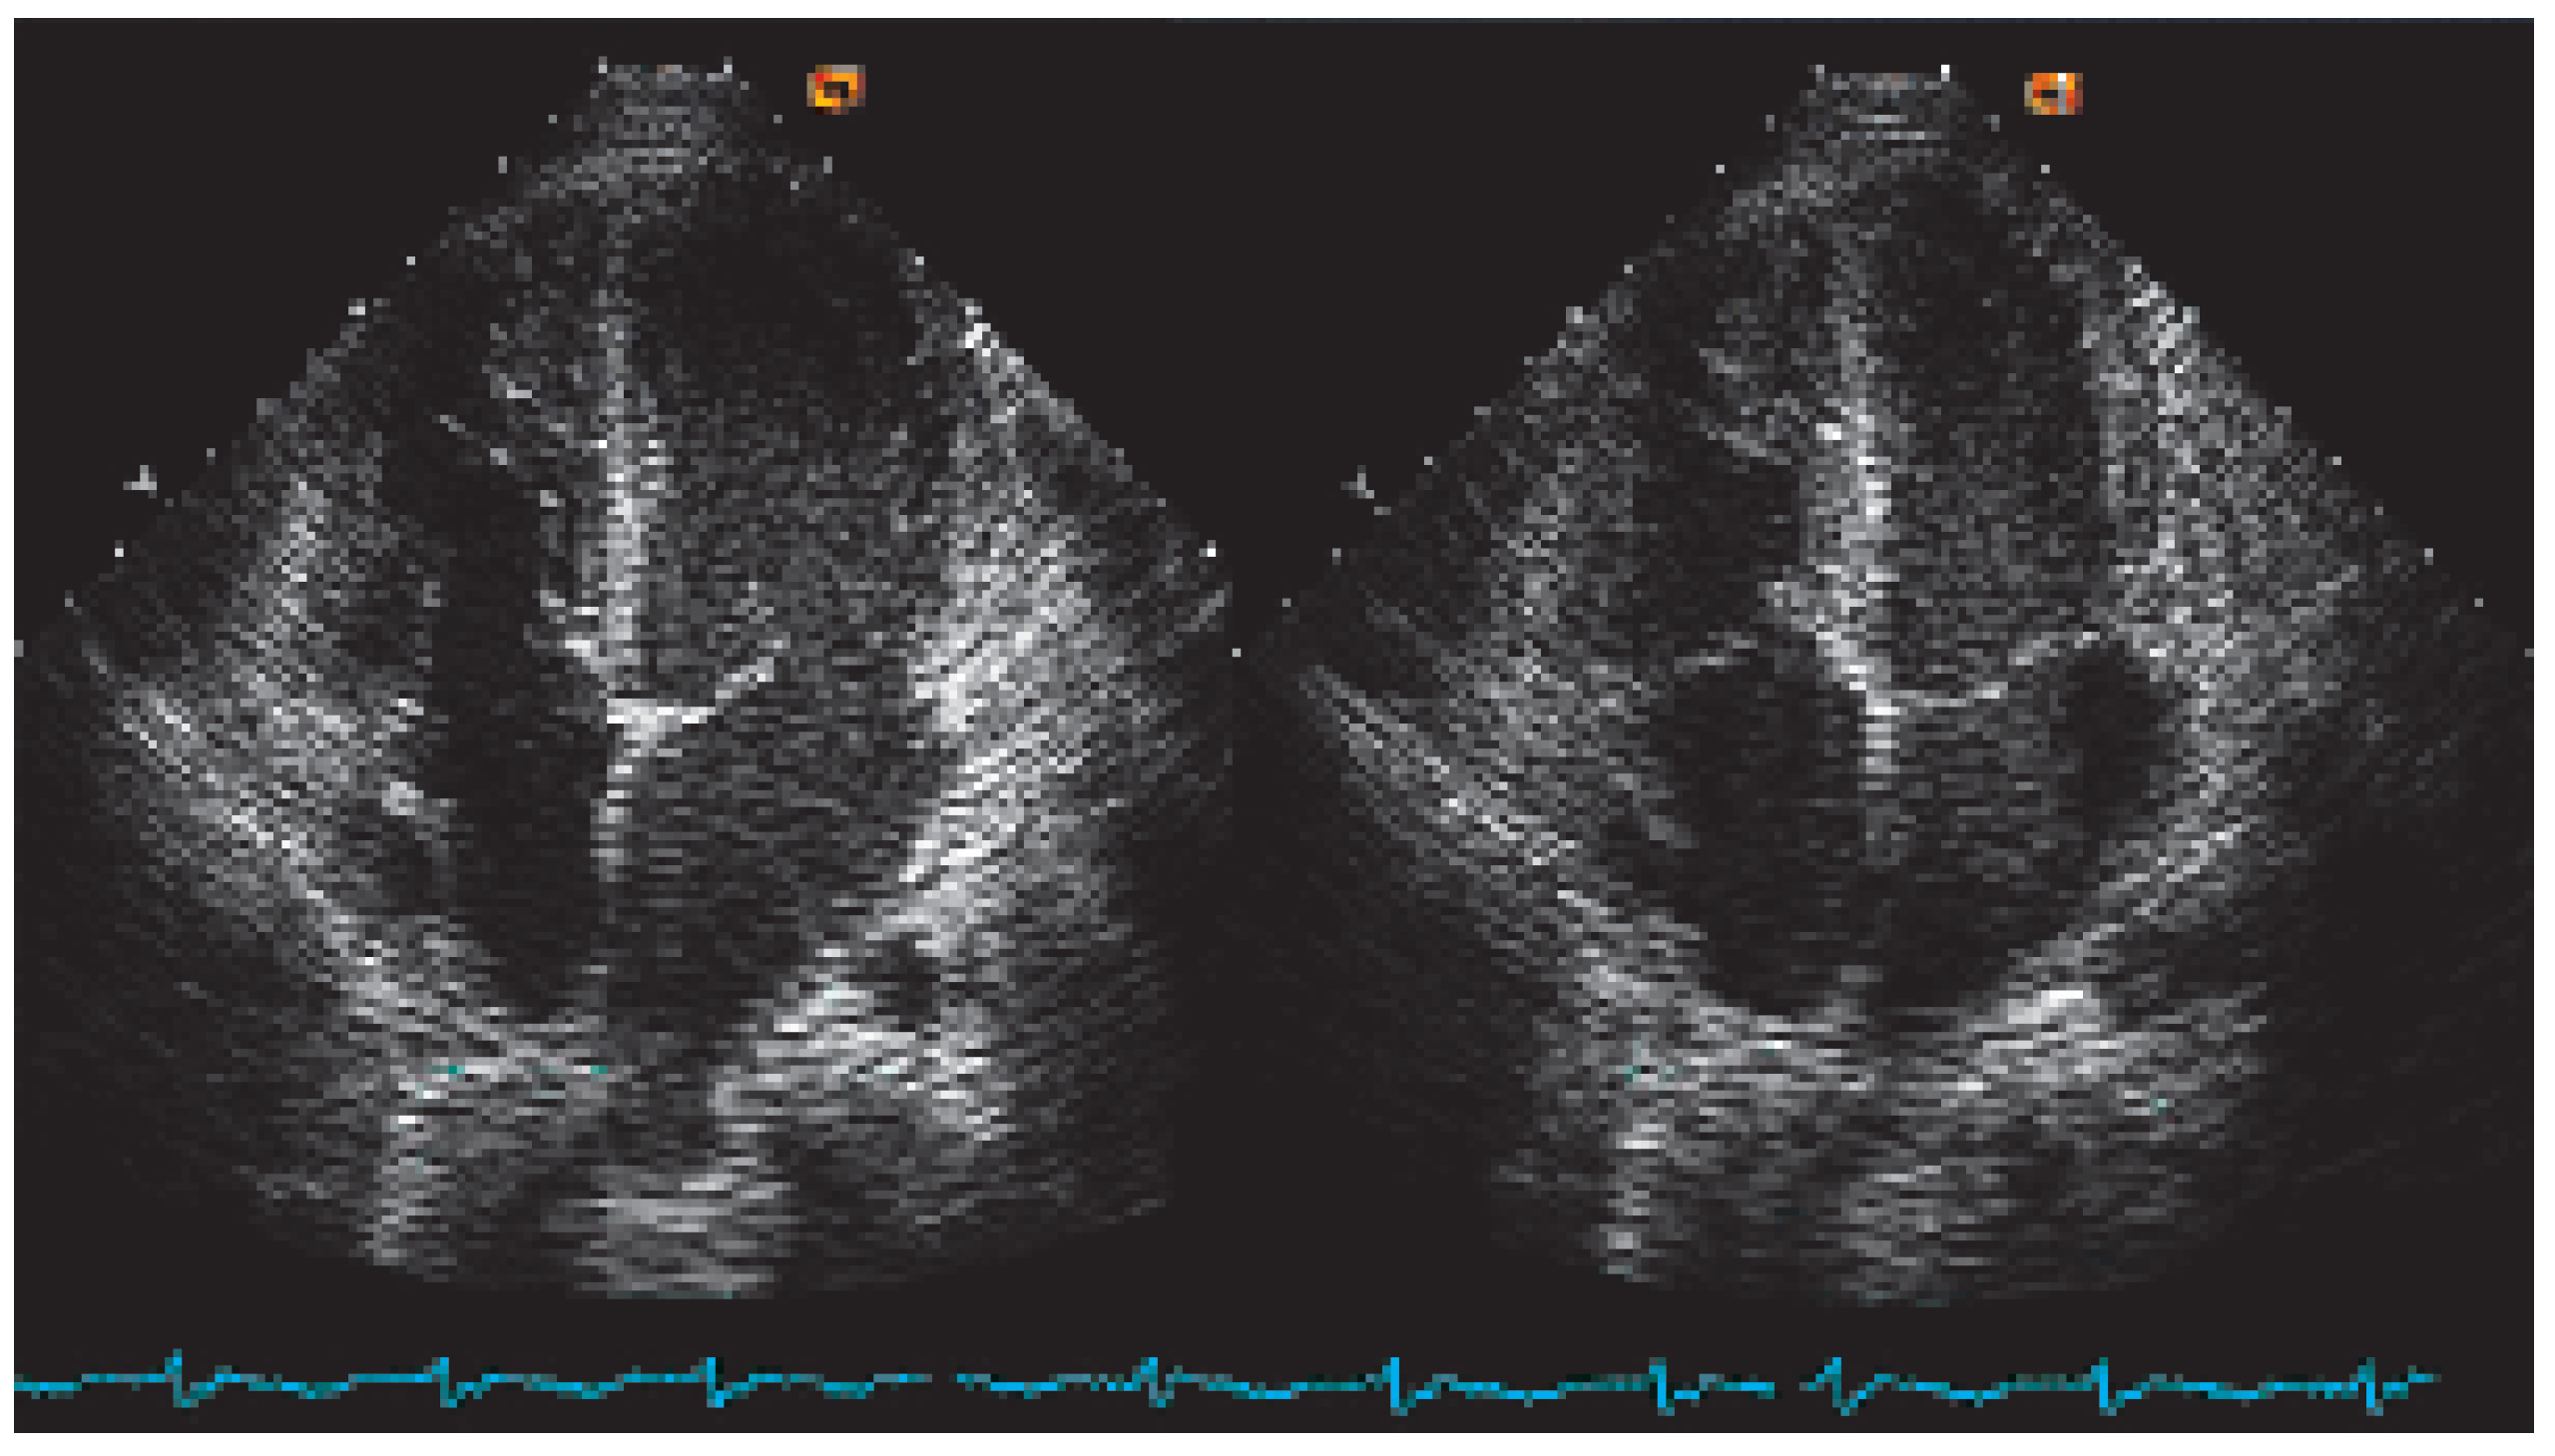

Figure 9. Aortic valve opening area with different types of operations or prosthesis. The red surface shows the opening area of various valves or prostheses and the echocadiographically measured gradient across the valve at rest are mentioned under each valve. Note that the “Ross procedure” (with a pulmonary valve slightly larger than a corresponding aortic one) presents the largest opening area.